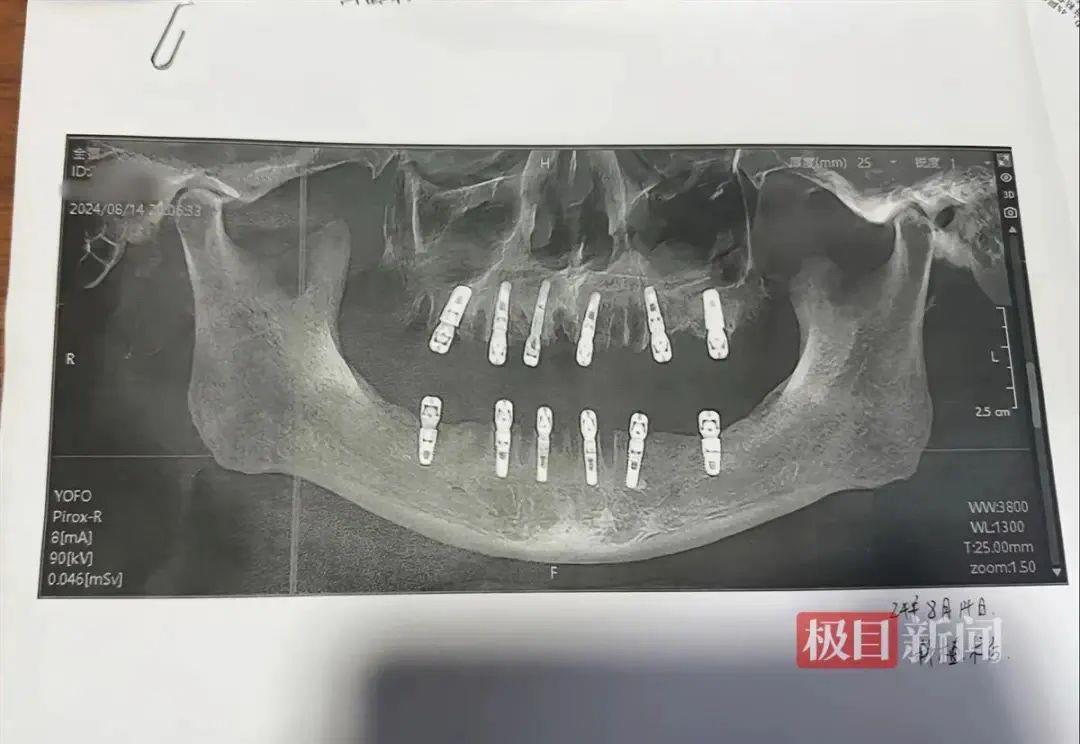

近日,浙江永康市一女士反映,其父亲在8月14日一天内拔除23颗牙齿并种植12颗牙齿,随后疼痛不止,13天后死亡。该消息随即引发热议。

当事人社交账号显示相关口腔影像资料。图源:极目新闻